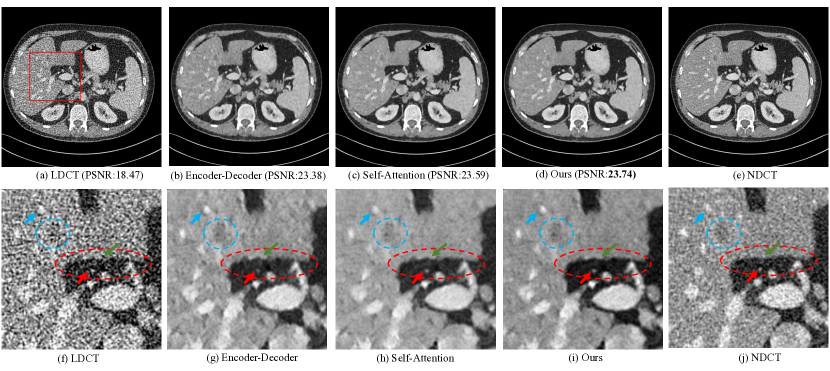

In this section, we explore the performance of different non-local models to show the advantages of our proposed 3D GCN module. As mentioned in Introduction section, CNN-based encoder-decoder model can extract non-local information by stacking downsampling operations. We thus construct a CNN-based encoder-decoder model (as the Baseline4), which has 3 downsampling layers and corresponding upsampling layers. Similarly, the self-attention-based model can leverage non-local relationships. Following [29], the self-attention CNN (SACNN) model with 3 self-attention layers (only plane attention module) is used for comparison, as the Baseline5. Based on our proposed GCN-MIF model, our proposed GCN-based model can be constructed by removing the module of contextual information (depth convolutional network). In addition, each baseline method is trained under two kinds of objectives. We evaluate the computational consumption (e.g., parameters, inference time, and GPU consumption), quantitative results, and visualized comparison on test set.

As reported in Table II, one can have some observations as following

Overall, as explicit non-local models, self-attention and GCN-based models outperform encoder-decoder-based model with an obvious margin (in terms of PSNR and SSIM), which validates the effectiveness of non-local modules.

Compared with self-attention-based model, our proposed GCN-based model achieves better performance under two loss functions, which is reasonable as the proposed GCN model can leverage appropriate non-local neighbors instead of all neighbors (e.g., self-attention). The negative impact of too many non-local information may be the reason why the performance slightly decreases.

For computational consumption, we can notice that our proposed GCN-based model can only take half of the running time and computational cost (e.g., GPU consumption) compared with self-attention-based model. This is obviously caused by the usage of the relationships of all the pixels for the self-attention module. Instead, the GCN module utilizes appropriate non-local information to achieve competitive performance.

The visualized comparison of denoising results (MSE-guided framework) is illustrated in the Figure 5. From the selected zoomed-in region of interest, we can notice some observations. First, for the noise suppression of the dark background area (as shown in red circle), the self-attention-based and our proposed GCN-based models have better capacity compared with encoder-decoder-based model, which may result from the introduction of non-local information as pointed by [29]. Second, compared with self-attention-based model, our proposed GCN-based model can retain more structural information (as pointed by blue arrow), we guess that it may be caused by too many non-local information, leading to the loss of their own information. The low attenuation lesion (as shown in blue circle) is maintained by our proposed model as much as possible. Finally, our proposed method produces the sharpest edge (as pointed by green arrow), which is reasonable as the selection of non-local neighbors can be along with the edge (as shown in the first sub-figure of Figure 4). Overall, our proposed GCN-based model has a better balance between noise reduction and structure preservation.